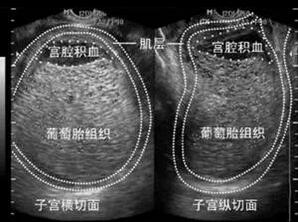

由于临床医生对于阴道出血、子宫增大且妊娠试验阳性的妇女多数怀疑为妊娠并发症,如先兆流产或稽留流产、异位妊娠,故详细确切的病史和全面的检查对妊娠滋养细胞疾病的正确诊断尤为重要。B超、MRI等影像学诊断也非常有价值,一般提示“宫腔蜂窝状改变”或“积雪征”。

图:盆腔MRI提示部分性葡萄胎(伴一发育正常胎儿)

多采用经阴道彩色多普勒超声检查,可检测到葡萄胎特征性超声表现。完全性葡萄胎的典型超声影像表现为:子宫明显大于孕周,宫内没有孕囊或胎心搏动,部分性葡萄胎有时可见胎儿或羊膜囊,但胎儿常合并畸形;侵润性葡萄胎通常表现为宫内1个或多个边界模糊的团块,含无回声区;绒毛膜癌表现为使子宫增大的不均质团块,这种不均质表现与坏死和出血区域对应,肿瘤可能会延伸到子宫旁组织;胎盘部位滋养细胞肿瘤表现为宫内胎儿可能存活,胎盘高回声团,团块通常侵及子宫肌壁。

(图:完全性葡萄胎超声图)